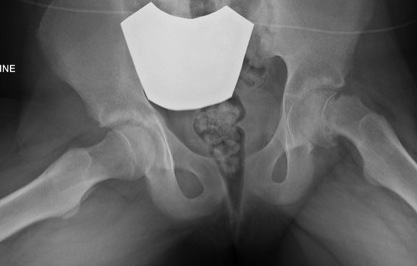

Lateral xray

Mild and moderate SCFE on left hips